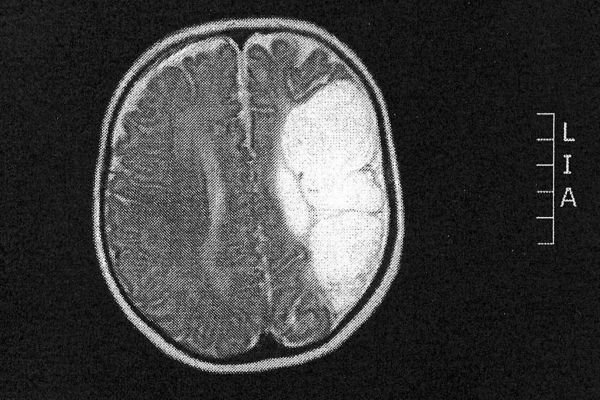

Rentgenski snimci (pogledajte sliku u galeriji) pokazali su da kod bebe, praktično, gotovo polovina mozga nedostaje. Lekarske prognoze bile su krajnje nepovoljne - doktori su upozorili roditelje da mali Džejk nikada neće biti u stanju da govori i hoda.

Uprkos najgorim lekarskim prognozama, mali Džejk Gledstoun je progovorio i hoda premda mu funkcioniše samo polovina mozga. Foto: LepaiSrecna